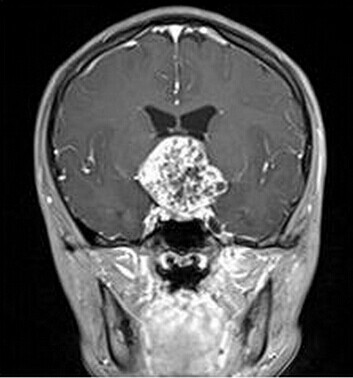

患者:男,15岁,双眼视力下降1年余,近来有嗜睡表现。

【正确答案】A 颅咽管瘤

(1)颅咽管瘤的两个发病高峰年龄分别是4-15岁和35-45岁,其中实性颅咽管瘤多见于成年人,本例为青少年患者,发病年龄无特异性;

(2)对诊断有提示意义的征象是明显强化,内散在微囊状不强化区。

[病理诊断] MRI6493:颅咽管瘤。